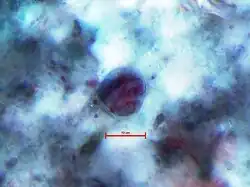

Fertige Zyste, E. histolytica

Fertige Zyste, E. histolytica -